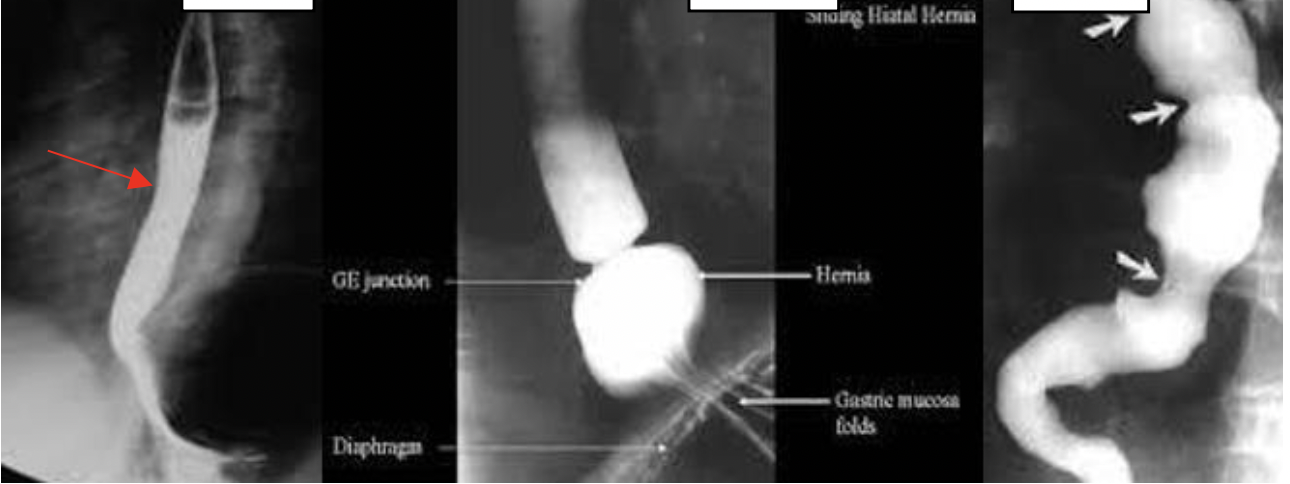

מה הבדיקה בתמונה ומה הפתולוגיות?

רדיוגרפיה של הושט, בולעים בריום.

אפשר לדמות ככה בקע סרעפתי.

Cork screw אפשר גם לזהות-

(התכווצויות לא סדירות של הושט)